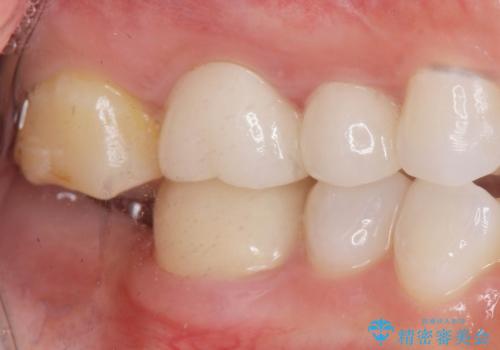

- 右下の歯を虫歯で抜去し、インプラント治療を希望され来院されました。

インプラントを埋入するのに十分な骨は存在しますが、放置した間に上の歯が伸びてきてしまいクラウンのスペース不足な状態です。